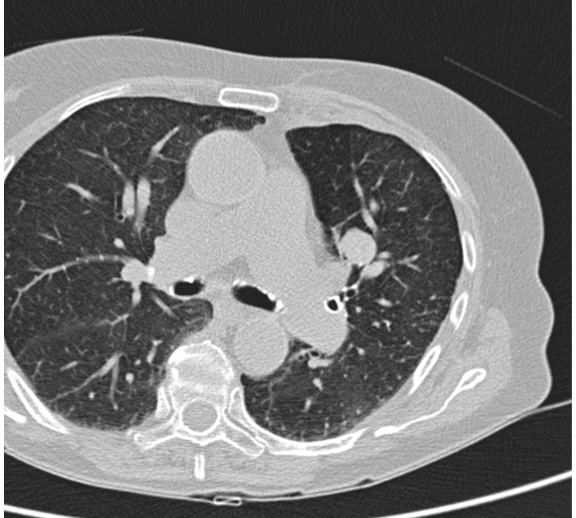

第一次CT扫描:观察引导针穿刺的方向和平面是否和靶病变一致(注意穿刺针的针尖不能停留在脏层胸膜表面,避免气胸)

第二次CT扫描:观察穿刺针在肺内的方向与平面是否与靶病变一致(注意每次针前进的距离是剩余针道的一半,以便随时纠正穿刺针前进的方向和水平)

引导针到病变的边缘

置换活检针

活检针进入病灶内活检,注意后方,针尖不要超过病灶的后界

拔针后显示沿针道少量肺实质出血